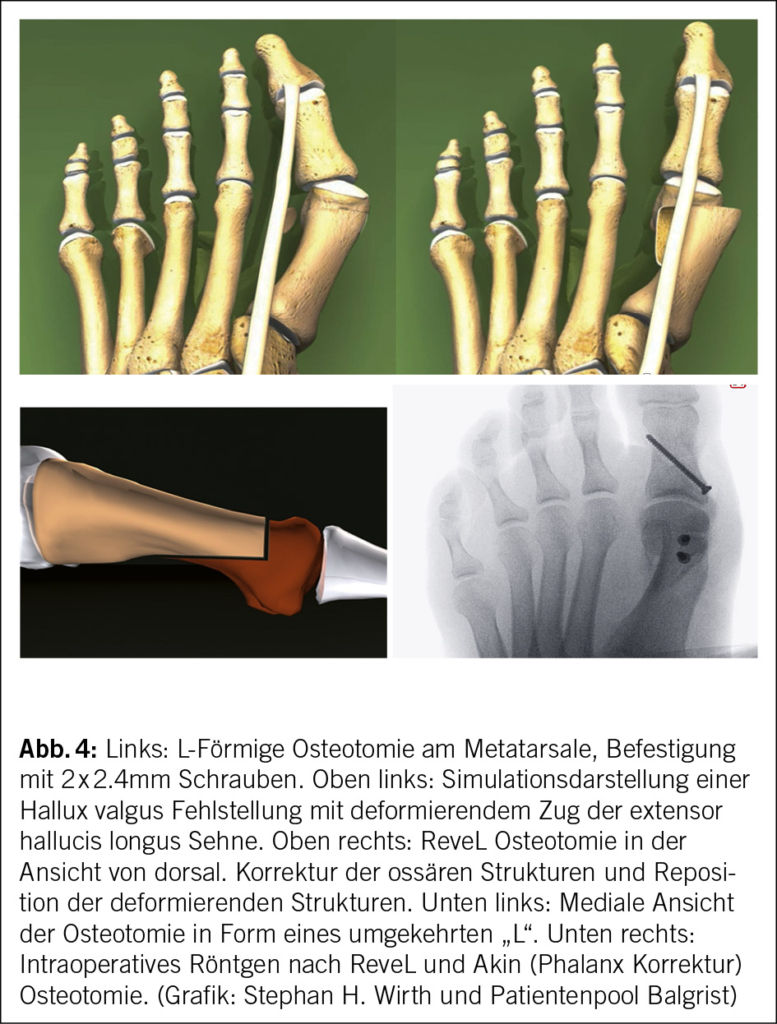

Handelt es sich um eine isolierte Hallux valgus Deformität oder besteht schon eine Degeneration am MTP können Metatarsale Ostoeomien durchgeführt, bei schweren Deformitäten, TMT I Hypermobilität oder auch rotationale Deformitäten sollten TMT I Arthrodesen durchgeführt werden (25). Zeigt das MTP eine schwere und symptomatische Degeneration auf, kann die Korrektur über eine MTP I Arthrodese angegangen werden. Eine der möglichen Osteotomieformen am Metatarsale I, welche sich über nun fast zwei Jahrzehnte bewährt hat, ist die «Reversed-L oder Reve-L» Osteotomie (25-27) (Abb. 4).